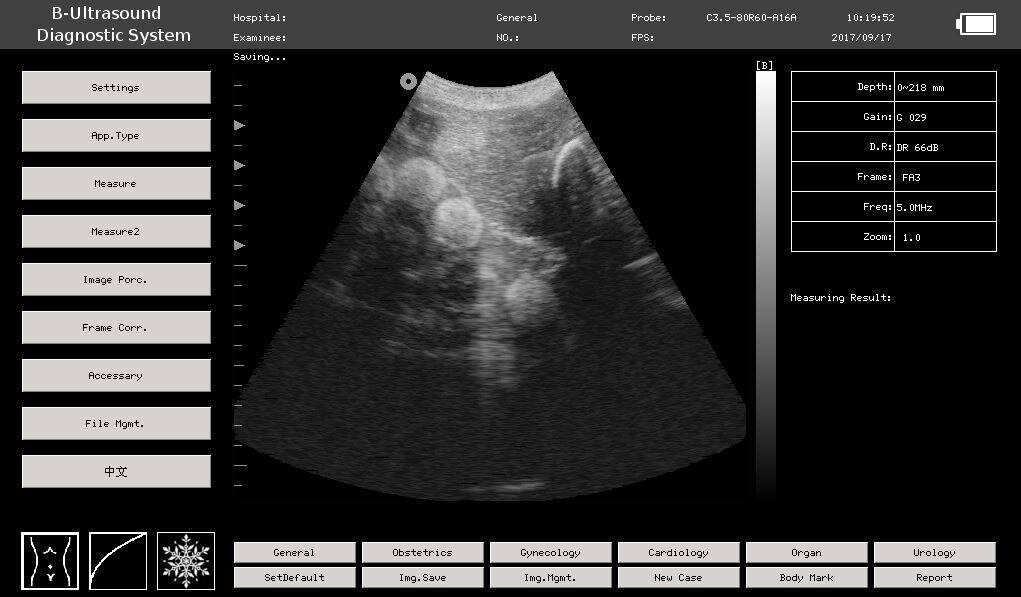

Can You See Eggs In Ultrasound. Web ovarian antral follicles can be identified and counted using transvaginal ultrasound (us) 1, 2. The number of antral follicles visible can give your doctor a ballpark sense of how many total eggs (including the many follicles still too small to see) you have remaining in your ovaries. Web antral follicles are very small — between 2 to 9 millimeters in diameter — but you can still see them on an ultrasound. Web “ultrasound is somewhat subjective, so you're still relying on someone's eyes to see and count, and it can vary somewhat between. Web follicular monitoring is the process of tracking growth of the ovarian follicles to identify maturation status of eggs. Since there is no test available to evaluate the true ovarian reserve 3, ovarian antral follicle count (afc) is accepted as a good surrogate marker 3, 4. They are only 100 microns (0.1 mm) in size, and can. Antral follicles are also referred. Web the main indicator of approaching ovulation, which can be well seen with ultrasound scanning, is a dominant. Web in reality, eggs are microscopic structures, which cannot be seen on ultrasound scans.

Web ovarian antral follicles can be identified and counted using transvaginal ultrasound (us) 1, 2. Web in reality, eggs are microscopic structures, which cannot be seen on ultrasound scans. Web follicular monitoring is the process of tracking growth of the ovarian follicles to identify maturation status of eggs. They are only 100 microns (0.1 mm) in size, and can. Web the main indicator of approaching ovulation, which can be well seen with ultrasound scanning, is a dominant. The number of antral follicles visible can give your doctor a ballpark sense of how many total eggs (including the many follicles still too small to see) you have remaining in your ovaries. Web antral follicles are very small — between 2 to 9 millimeters in diameter — but you can still see them on an ultrasound. Web “ultrasound is somewhat subjective, so you're still relying on someone's eyes to see and count, and it can vary somewhat between. Since there is no test available to evaluate the true ovarian reserve 3, ovarian antral follicle count (afc) is accepted as a good surrogate marker 3, 4. Antral follicles are also referred.

Can You See Eggs In Ultrasound Antral follicles are also referred. Web in reality, eggs are microscopic structures, which cannot be seen on ultrasound scans. Web “ultrasound is somewhat subjective, so you're still relying on someone's eyes to see and count, and it can vary somewhat between. Web antral follicles are very small — between 2 to 9 millimeters in diameter — but you can still see them on an ultrasound. Web ovarian antral follicles can be identified and counted using transvaginal ultrasound (us) 1, 2. Since there is no test available to evaluate the true ovarian reserve 3, ovarian antral follicle count (afc) is accepted as a good surrogate marker 3, 4. Antral follicles are also referred. The number of antral follicles visible can give your doctor a ballpark sense of how many total eggs (including the many follicles still too small to see) you have remaining in your ovaries. Web follicular monitoring is the process of tracking growth of the ovarian follicles to identify maturation status of eggs. They are only 100 microns (0.1 mm) in size, and can. Web the main indicator of approaching ovulation, which can be well seen with ultrasound scanning, is a dominant.